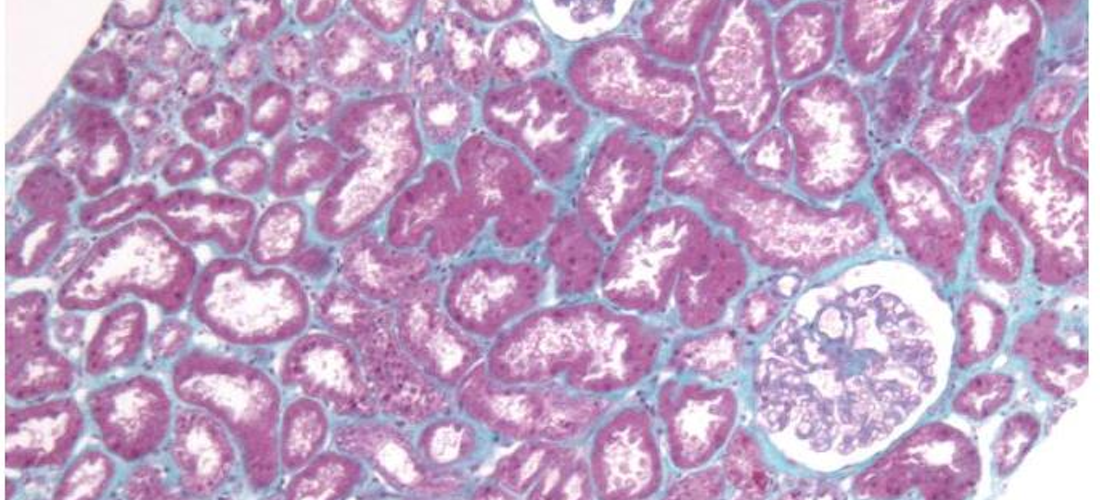

- Biopsie rénale récente (< 4 semaines) confirmant l'atteinte rénale active de la vascularite associée aux ANCA.